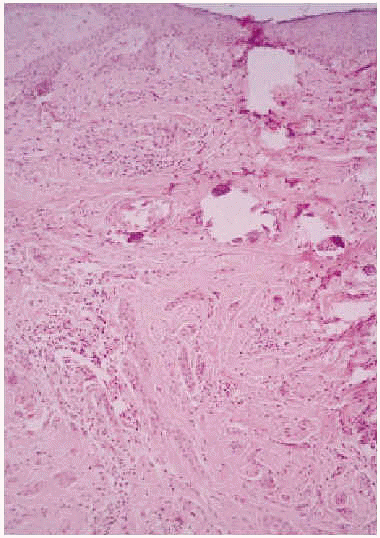

Se realizó una biopsia de la lesión y el estudio histopatológico mostró una proliferación de células basaloides formando nidos y cordones sin conexión con la epidermis e inmersas en una estroma densa, fibrosa e hialinizada (fig. 1). En la dermis superficial se apreciaban ocasionales microquistes de queratina con calcificación (fig. 2). Las células epiteliales se distribuían formando nidos y cordones, tenían una marcada diferenciación ductal y patrón infiltrativo, y afectaban al tejido celular subcutáneo, el músculo estriado mostrando también invasión del espacio perineural (fig. 3). Las células eran de pequeño tamaño, con ligero pleomorfismo, núcleos ovoides con nucléolo evidente y con citoplasma claro, a veces marcadamente vacuolado y contenían focalmente un material PAS (ácido peryódico de Schiff) positivo diastasa resistente (fig. 4).

Fig. 1.--Nidos y cordones celulares en dermis, sin conexión con la epidermis, inmersos en una estroma densa y fibrosa (HE, x10).